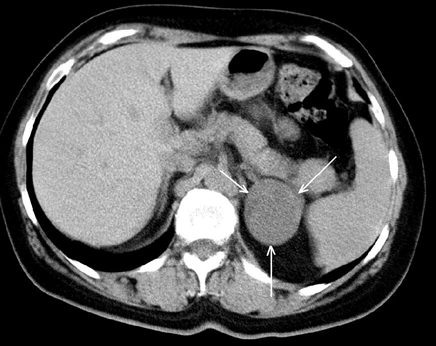

Важное место среди инструментальных методов исследования опухолей надпочечников в настоящее время занимает УЗИ (рис. 1). Это, в первую очередь, обусловлено простотой его выполнения, высокой достоверностью полученных результатов, а также быстротой и доступностью его выполнения (Демидов В.Н. и др., 1991). По мнению большинства авторов, УЗИ позволяет выявить опухоли надпочечников при минимальном диаметре от 1 до 2 см (Gunhter R.W., 1984; Zografos G.C. et al., 1994).

Рисунок 1. УЗИ — опухоль правого надпочечника

Значительно улучшает качество диагностики опухолей надпочечников использование КТ. Минимальная величина опухоли, определяемая этим методом, составляет от 0,5 до 1 см (Бондаренко В.О., 1986). КТ позволяет определить топографию надпочечников, форму, величину, структуру. Точность КТ в диагностике опухолей надпочечников в настоящее время составляет 80–95,7% (Авдеева Т.Ф. и др., 1992) (рис. 2).

Рисунок 2. КТ — опухоль (аденома) левого надпочечника